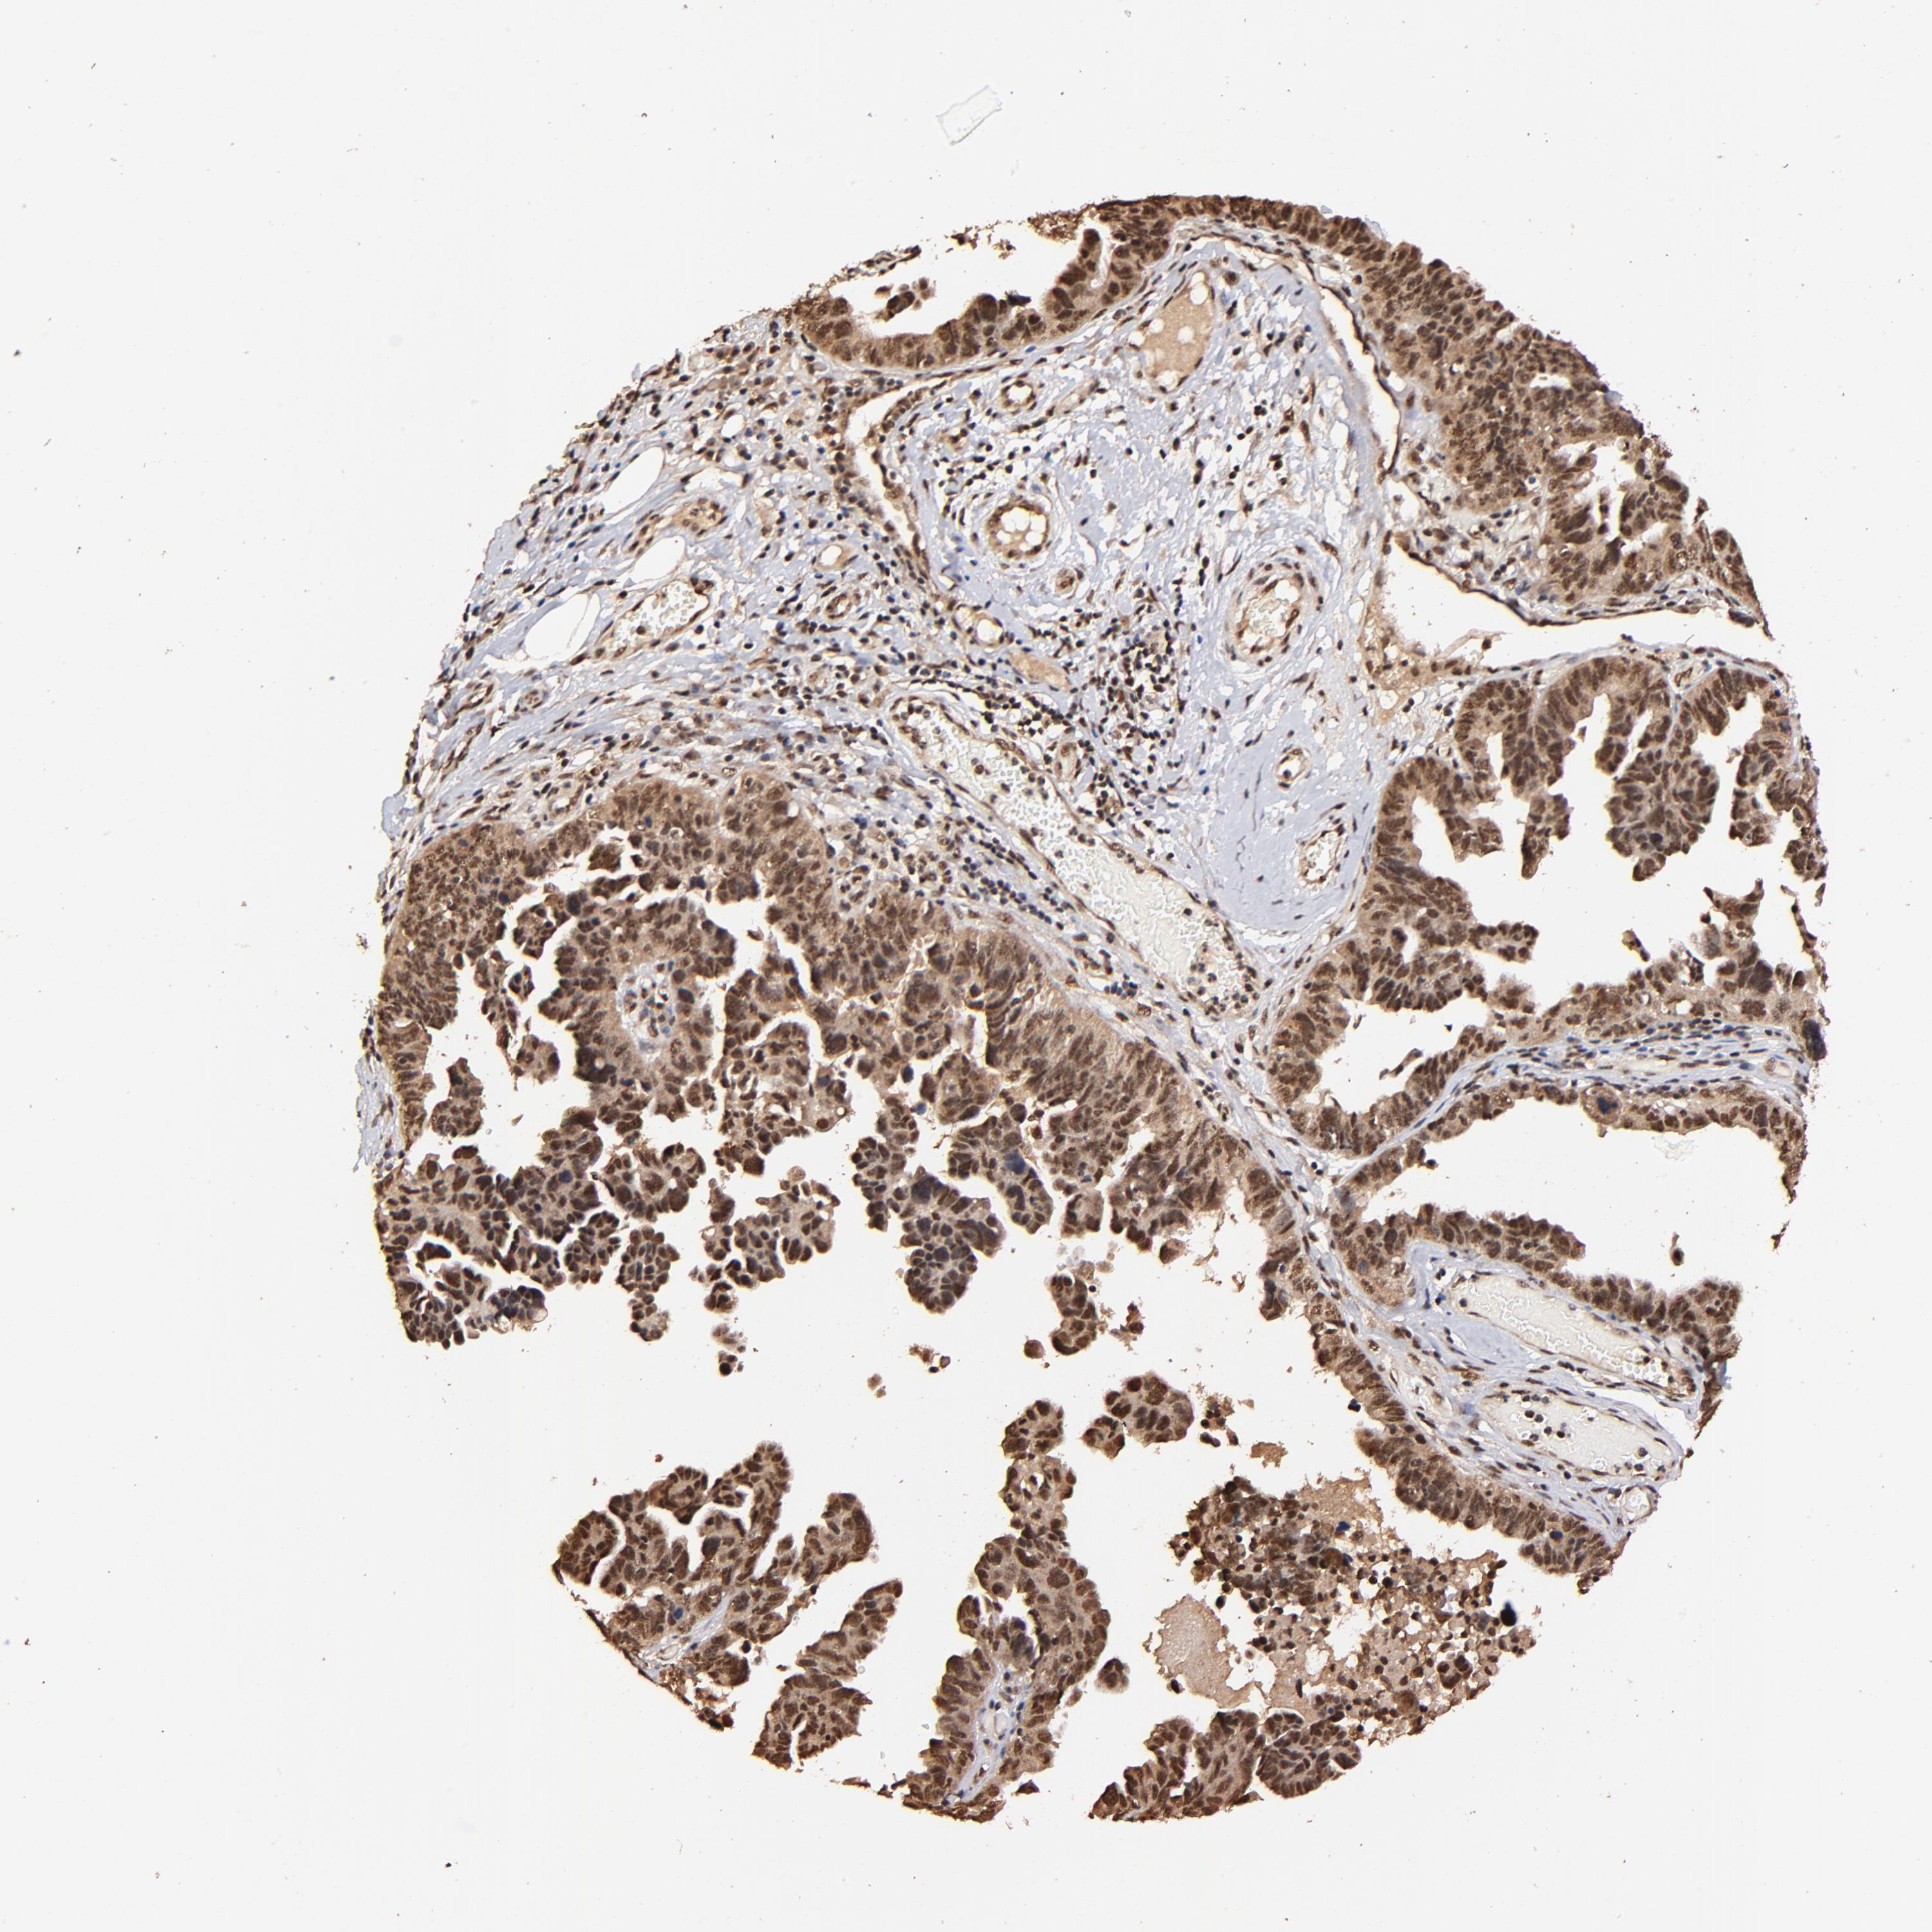

OVARIAN CANCER - Protein expressioni

A mouse-over function shows sample information and annotation data. Click on an image to view it in a full screen mode. Samples can be filtered based on level of antibody staining by selecting one or several of the following categories: high, medium, low and not detected. The assay and annotation is described here.

Note that samples used for immunohistochemistry by the Human Protein Atlas do not correspond to samples in the TCGA dataset.

Antibody stainingi

Antibody staining in the annotated cell types in the current human tissue is reported as not detected, low, medium, or high, based on conventional immunohistochemistry profiling in selected tissues. This score is based on the combination of the staining intensity and fraction of stained cells.

Each image is clickable and will lead to virtual microscopy that enables deeper exploration of all samples and also displays staining intensity scores, fraction scores and subcellular localization as well as patient and tissue information for each sample.

Antibody HPA003184

Antibody HPA003185

Staining

High

Medium

Low

Not detected

Intensity

Strong

Moderate

Weak

Negative

Quantity

>75%

75%-25%

<25%

None

Location

Nuclear

Cytoplasmic/membranous

Cytoplasmic/membranous,nuclear

Cystadenocarcinoma, mucinous, NOS

Carcinoma, endometroid

Cystadenocarcinoma, serous, NOS